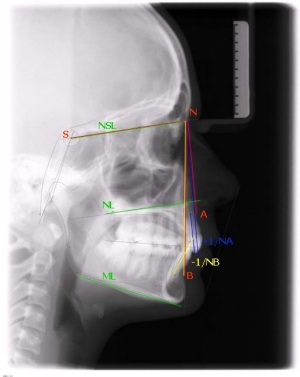

seitliche Röntgenaufnahme (FRS) zur Beurteilung

der Zahn- und Kieferlage im Schädel und

Erstellung einer Wachstumsprognose